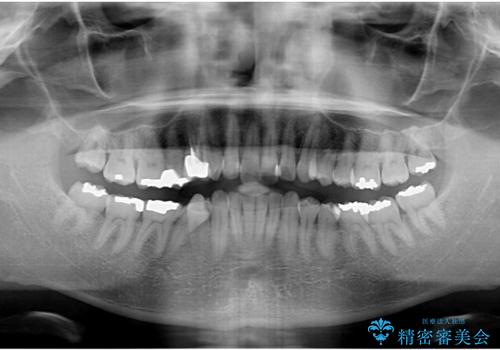

- 外に飛び出した側方の歯と、前歯のデコボコを気にして来院された患者様です。

IPR(歯と歯の間を削る)によってデコボコが解消するように設計し、インビザラインにより治療を行うこととしました。

治療途中で1年半以上通院されない時期があったため、後戻りが生じたことで治療期間が長くなってしまいました。

親知らずを抜去したことで、下顎のデコボコがきれいに解消されました。